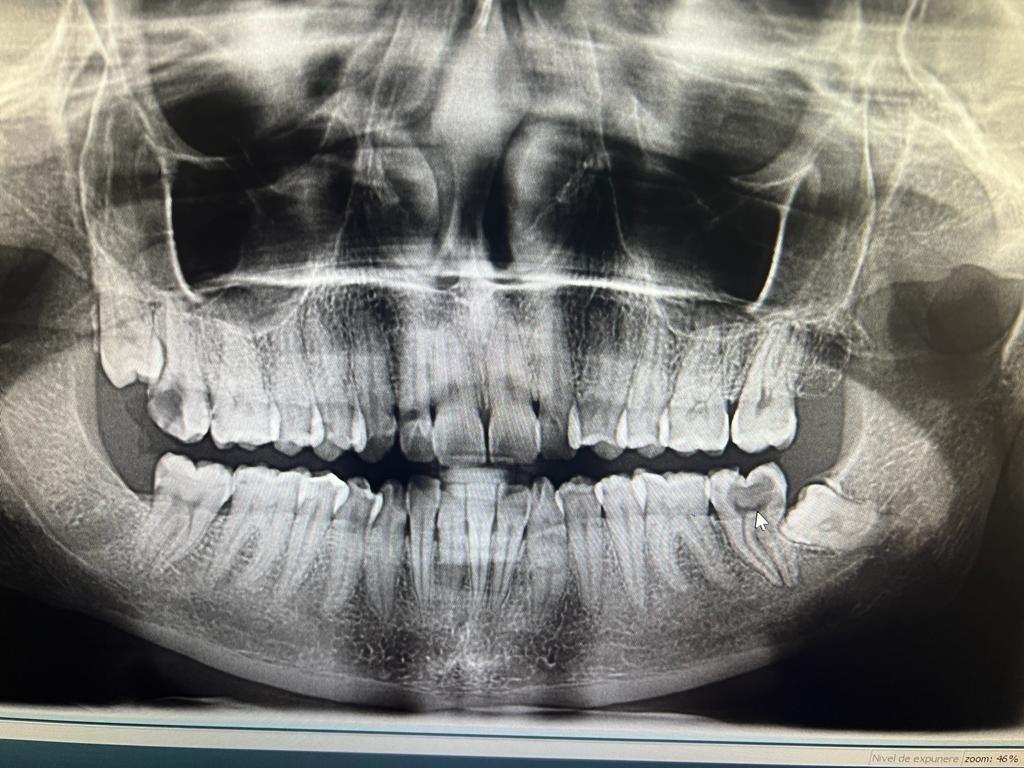

In urma unui consult dentar, medicul stomatolog stabileste primii pasi pentru implantul dentar: examen radiologic si analize de sange. La examenul radiologic se obtin informatii exacte despre cantitatea de os care urmeaza sa primeasca implantul dentar. Tot acum se poate stabili daca este nevoie de o eventuala aditie osoasa. Implantul se lasa in os intre 4 – 6 luni.